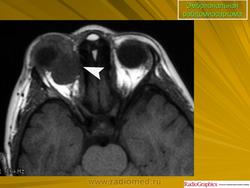

Рабдомиосаркома — чрезвычайно агрессивная опухоль орбиты, является наиболее частой причиной злокачественного роста в орбите у детей. Мальчики болеют почти в 2 раза чаще. Источником роста рабдомиосаркомы являются клетки скелетных мышц. Выделены три типа опухоли: эмбриональный, альвеолярный и плеоморфный, или дифференцированный. Последний тип встречается редко. У детей до 5 лет чаще развивается эмбриональный тип опухоли, после 5 лет — альвеолярный. Как правило, рабдомиосаркома состоит из элементов нескольких типов (смешанный вариант). Точный диагноз можно установить только на основании результатов электронной микроскопии.

Излюбленная локализация опухоли — верхневнутренний квадрант орбиты, поэтому в процесс рано вовлекаются мышца, поднимающая верхнее веко, и верхняя прямая мышца. Птоз, ограничение движений глаза, смещение его книзу и книзу кнутри — это первые признаки, на которые обращают внимание как сами больные, так и окружающие лица. У детей экзофтальм или смещение глаза при локализации опухоли в переднем отделе орбиты развивается в течение нескольких недель (рис. 20.23, а). У взрослых опухоль растет медленнее, в течение нескольких месяцев. Быстрое увеличение экзофтальма сопровождается появлением застойных изменений в эписклеральных венах, глазная щель полностью не смыкается, отмечаются инфильтраты на роговице и ее изъязвление. На глазном дне — застойный диск зрительного нерва. Первично развиваясь вблизи верхневнутренней стенки орбиты, опухоль быстро разрушает прилежащую тонкую костную стенку, прорастает в полость носа, вызывая носовые кровотечения. Ультразвуковое сканирование, компьютерная томография, термография и тонкоигольная аспирационная биопсия — это оптимальный диагностический комплекс инструментальных методов исследования при рабдомиосаркоме (рис. 20.23, б). Лечение комбинированное. Протокол лечения предусматривает предварительное проведение полихимиотерапии в течение 2 нед, после чего проводят наружное облучение орбиты. После комбинированного лечения более 3 лет живут 71 % больных.